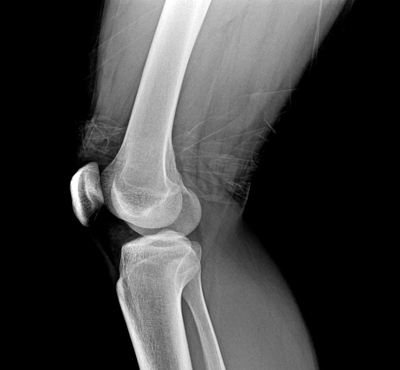

Osteoarthritis patients can broadly be divided into three groups according to the location of the joint affected, with most patients suffering from OA of the hand joints, followed by OA of the knee and hip (Figure 1). Although we are currently developing TG-C to treat the knee OA application, as shown in figure 1 there are still large populations of individuals affected by OA in other joints who may be able to benefit from treatment with TG-C. TG-C has been tested in the U.S. for safety and efficacy as an OA treatment of the knee through Phase II clinical trials. Phase III clinical trials in the U.S. are currently in the two-year follow-up period. Additionally, TG-C-K has also completed Phase III clinical trials in South Korea. Based upon TG-C promising results in targeting OA of the knee, Kolon TissueGene is planning to expand the indications for TG-C through additional clinical trials to include both OA of the hand and hip. Successful completion of these trials will allow many individuals currently suffering from the severe pain, swelling and stiffness associated with OA to experience decreased pain and improved function through treatment with TG-C.